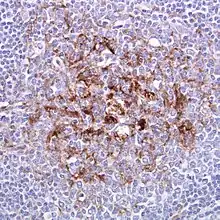

Biopsy of the tonsil in variant CJD. Prion protein immunostaining. | |

Examination of brain tissue is required to confirm a diagnosis of variant CJD.[2] The following confirmatory features should be present:[2]

- Numerous widespread kuru-type amyloid plaques surrounded by vacuoles in both the cerebellum and cerebrum – florid plaques.[2]

- Spongiform change and extensive prion protein deposition shown by immunohistochemistry throughout the cerebellum and cerebrum.[2]